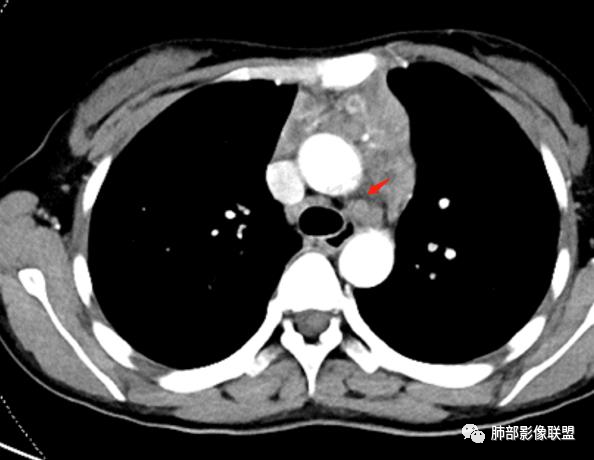

2.影像显示前纵隔不规则块状影,依势贴附心脏大血管旁,密度不均,边界不甚清楚,有结节融合感。

3.病灶轻度不均匀强化,可见血管穿行,散在液性低密度区。

双肺门未见肿大淋巴结。

4.双侧腋窝区见增大淋巴结,边界清楚。